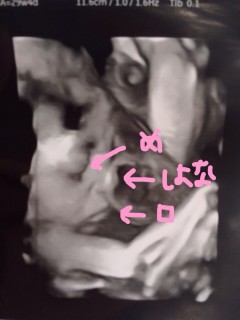

1415gの女の子。今日顔を見せてくれたのは双子の妹の方です。 鼻が低くて口がとがっているところが私にそっくりです☆